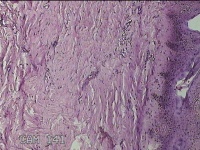

右下腹部切口结节

性别

女

年龄

27岁

临床诊断

皮下结节

一般病史

发现右下腹部切口结节10余年。

标本名称

大体所见

灰白暗红色带皮肤样结节2.3x1.3x0.8cm一个。表面糜烂,切面灰白色,质硬。

需要侵袭性纤维瘤病和纤维瘢痕鉴别一下